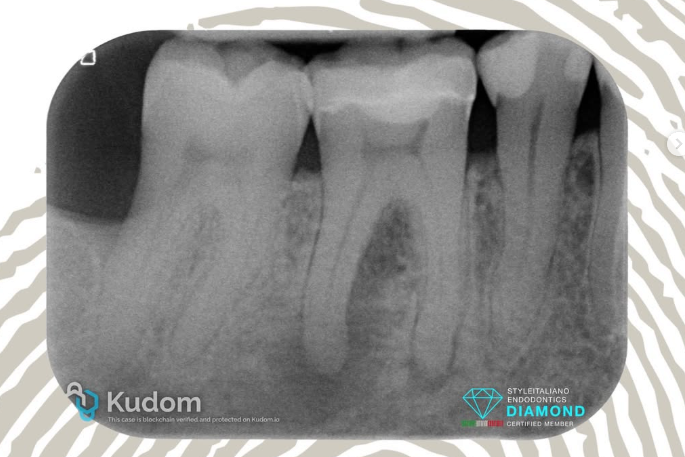

4.6: SINGLE VISIT RETREATMENT - L.E.O - 7 YEARS RECALL

A large periapical lesion was present on the mesial root of tooth 4.6, which had been previously treated many years ago and restored with a fiber post and crown.

The patient requested that the retreatment be performed through the crown, despite being informed that this was not the ideal approach.

After removal of the fiber post using an ultrasonic tip, the tooth was desobturated with rotary files, then shaped, thoroughly cleaned, and obturated in the same session.

CeraSeal bioceramic sealer was used with the Cold Hydraulic Condensation (CHC) technique, as the tooth was asymptomatic and no exudate was present in the canal.

The 1-year recall showed the not yet completed healing of the lesion and a fracture of the crown.

At the 7-year recall, complete healing of the large lesion was observed — it’s all about the outcome.

ARE BIOCERAMIC SEALER AND CHC RELIABLE? IT’S ALL ABOUT OUTCOME, NO FOLLOW UP NO ENDO.